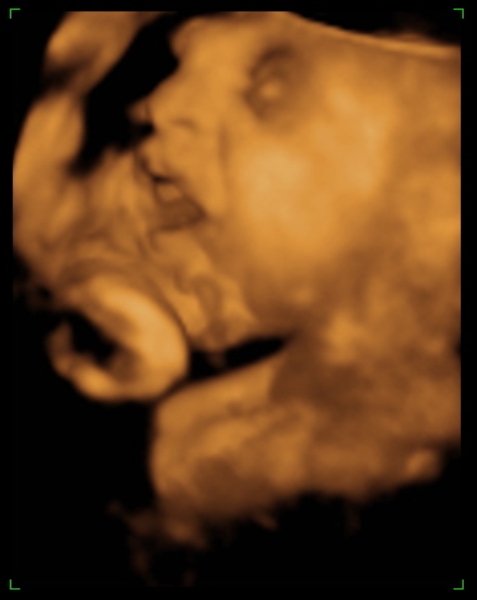

Tegnap megjártuk a 4D-t, nagyon szép husis a kisasszony :lol: persze aludt, nem kommunikált velünk, akármit ettem, ittam, csináltam. :lol: De azért féloldalasan aludt, úgyhogy csak láthattuk, volt mosoly, ásítás, fintor :lol: :lol:

Ja, és itt is megállapították, hogy nagy a talpa :lol: :lol: :lol: És a fejecskéje is, úgyhogy azt mondták majd megdolgoztat szülésnél, gondoltam "tök jó" :lol: :roll:

Méretek:

BPD - 8,17 cm

HC - 31,02 cm

AC - 28,59 cm

FL - 6,36 cm

Tappancs - 7,1 cm :lol: :lol: (s azt mondta a nő, hogy a talp általában ugyan akkora, mint az FL, tehát Dorkáé, nagy pacsker :lol: )

Becsült súly: 2078 gramm

Azt mondta, hogy ha 40 hétig bent marad, akkor 3400-3600 gramm körüli baba lesz. És tankönyv szerint halad gyarapodásban :lol: . Jaaa, és lesz haja:lol:

Ja, és a képek lemaradtak :D

Kép mosolygom:)

Kép ásítok, UFO nyitott szemeimmel:))))

Kép profilból

Kép nagy tapppppancsom:)

Kép

Persze a kis keze mindenhol ott van :lol: Bocsi, ha picit sok voltam :oops: 8)